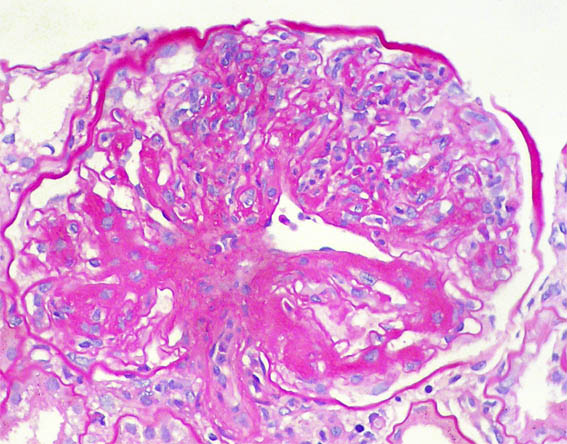

Figura 7.

PAS, X400.